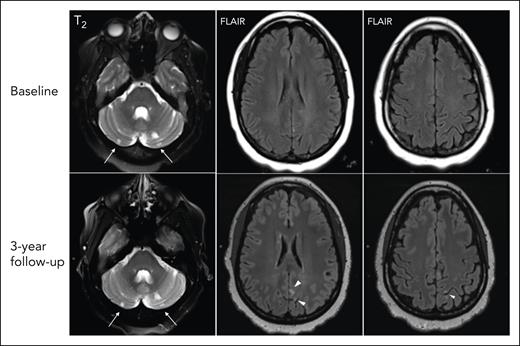

SCI were observed in 18 of 36 (50%) participants who completed the study MRI. None of the participants had a nonsilent infarct at the time of evaluation. Figure 2 shows examples of varied brain MRI findings in patients with iTTP, including normal imaging (Figure 2A), SCI manifesting as small FLAIR hyperintense lesions (>3 or 5 mm in length) involving the cortical or subcortical region and deep white matter (Figure 2B), smaller scattered punctate FLAIR hyperintense lesions in the subcortical and deep white matter attributed to nonspecific chronic small vessel ischemic changes (Figure 2D), and extensive and confluent FLAIR hyperintensity in the periventricular and deep white matter (Figure 2C). Among patients with SCI, 8 of 18 (44.4%) had a history of overt stroke, including 3 patients who had stroke during an acute iTTP episode, whereas 10 of 18 (55.6%) did not have a history of clinically overt stroke. Thus, even among some patients with a clinical history of stroke, new SCIs were detected with study MRIs. Figure 3 shows such an example of a 46-year-old woman (patient 1) who had an initial clinical MRI performed for dizziness that started during the iTTP episode but persisted for 3 months after achieving clinical remission; this MRI showed evidence of small chronic infarcts in bilateral cerebellar hemispheres. A research MRI performed 3 years later demonstrated multiple, small, chronic cortical infarcts that were new, without corresponding focal neurological deficits. She did not have any intercurrent iTTP episodes between the 2 MRIs. Her ADAMTS13 activity had been monitored every 3 months in remission and ranged from 38% to 100% (average, 72%; reference range, 70%-150%). Although she did not receive preemptive rituximab, she did receive immunosuppression for systemic lupus that might have led to improvement in ADAMTS13 activity.

Brain MRI findings of incident SCI since prior stroke. At baseline (top), small chronic infarcts in the cerebellar hemispheres are well depicted on T2 weighted sequences (arrows) of a MRI done in routine clinical care for dizziness persisting 3 weeks after achieving clinical remission after a first iTTP episode, which were unchanged on the follow-up research scan. At 3-year follow-up, upon the research MRI (bottom), there are multifocal new small chronic infarcts in the left parietal cortical regions seen on axial FLAIR images (arrowheads).